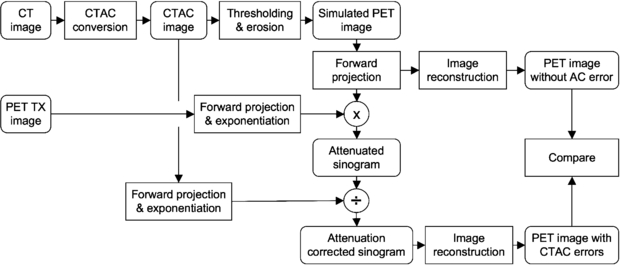

The effect of incorrect CTAC factors was determined by forward-projecting the simulated PET image, including attenuation (by using the inverse of the 'true' attenuation correction factors obtained from the PET transmission scan), and correcting for attenuation with the 'erroneous' attenuation correction factors (obtained from the CTAC image). The attenuation corrected data were then reconstructed with FBP. The process is outlined in figure 5.

Figure 5. Flowchart of the process followed to evaluate the bias in PET image quantification due to inaccuracies in the CTAC data using the reconstructed images of the bovine femur phantom.

Download figure:

Standard imageFor a reference image, we forward-projected and reconstructed the simulated emission data. In this manner the sampling and resolution effects were the same for the two PET emission images. The numerical results calculated were the per cent error in the average SUV within each region between the PET emission images using the PET TX scan (SUVTX) and CTAC scan (SUVCTAC) attenuation correction factors as follows:

2.3. Experiment 3: sensitivity analysis using patient emission images

In the third experiment, we used CT and PET images from five patient exams with significant FDG uptake in bone tissue. Similar to experiment 2, we measured the bias of the FDG uptake due to simulated errors in attenuation correction. The experimental process is outlined in figure 6. Since patients were imaged only on the PET/CT scanner (figure 7 shows one of these studies), 511 keV PET TX images were not available. For these patient exams we used the measured LACCTAC and SUV images as the reference standards.

Figure 6. Flowchart of the process followed to evaluate the bias in tumor quantification due to inaccuracies in CTAC data. 'CT image' and 'PET SUV image' are the reconstructed images for each patient.

Download figure: